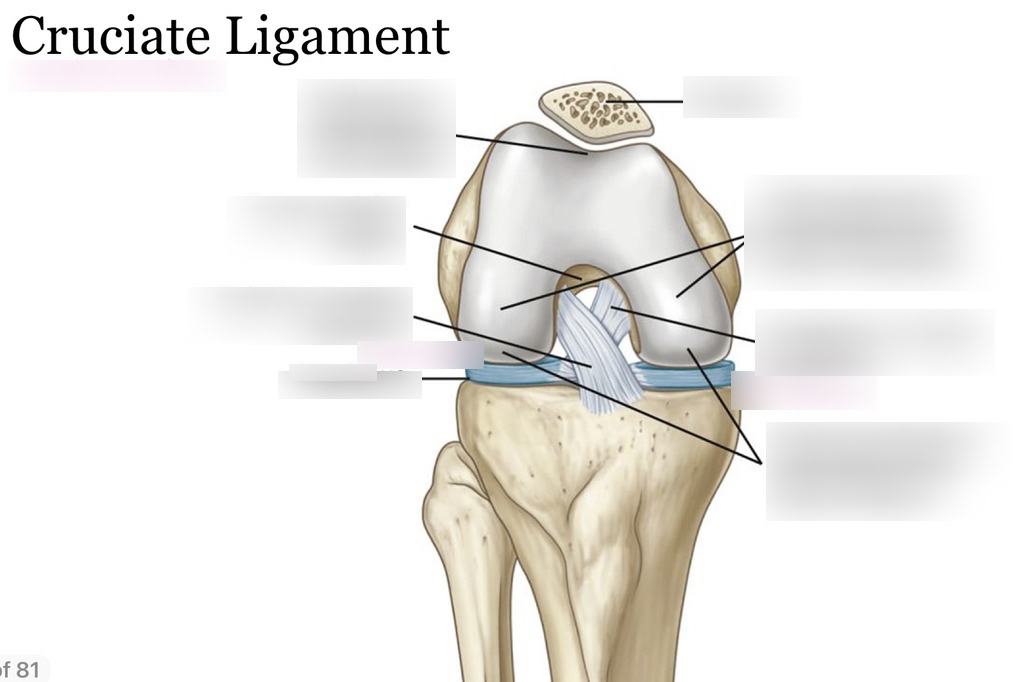

What is Cruciate Ligament Repair and Reconstruction?

Ligaments are tough bands of tissue that connect bones and stabilize joints. Injuries to ligaments, such as Cruciate ligament tears (ACL or PCL), ruptures, or other ligament damage, are common in sports, accidents, and falls. Ligament repair involves surgically reattaching or reconstructing the damaged ligament to restore stability, while ligament reconstruction uses grafts (from the patient or donor tissue) to replace the damaged ligament entirely.

Anterior Cruciate Ligament (ACL) tears – one of the most common cruciate ligament injuries

Posterior Cruciate Ligament (PCL) injuries – crucial for knee stability